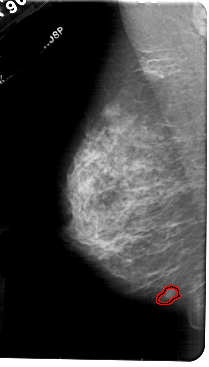

A_1842_1.LEFT_CC

LEFT_CC LINES 5206 PIXELS_PER_LINE 2746 BITS_PER_PIXEL 12 RESOLUTION 43.5 OVERLAY

FILE: A_1842_1.LEFT_MLO.OVERLAY

TOTAL_ABNORMALITIES 1

ABNORMALITY 1

LESION_TYPE MASS SHAPE LOBULATED MARGINS CIRCUMSCRIBED

ASSESSMENT 4

SUBTLETY 3

PATHOLOGY BENIGN

TOTAL_OUTLINES 1

BOUNDARY